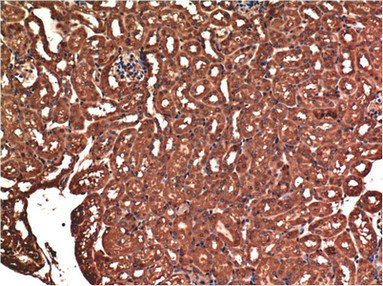

• Immunohistochemical analysis of paraffin-embedded Mouse Kidney Tissue using CSB-MA484077 at dilution of 1:200.